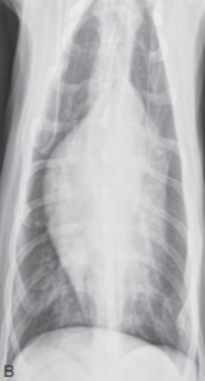

| Generalized cardiomegaly |

|---|

| RA, RV, LA, LV๊ฐ ๋ค ์ปค์ง โ Globoid heart |

| - Pericardial effusion - ์ฌํ ์์ชฝ ์ฌ์ฅ๋ณ (MVI + TVI) - PPDH (Peritoneopericardial diaphragmatic hernia) - Cardiomyopathy (DCM) - Anesthesia, bradycardia |

![]() |